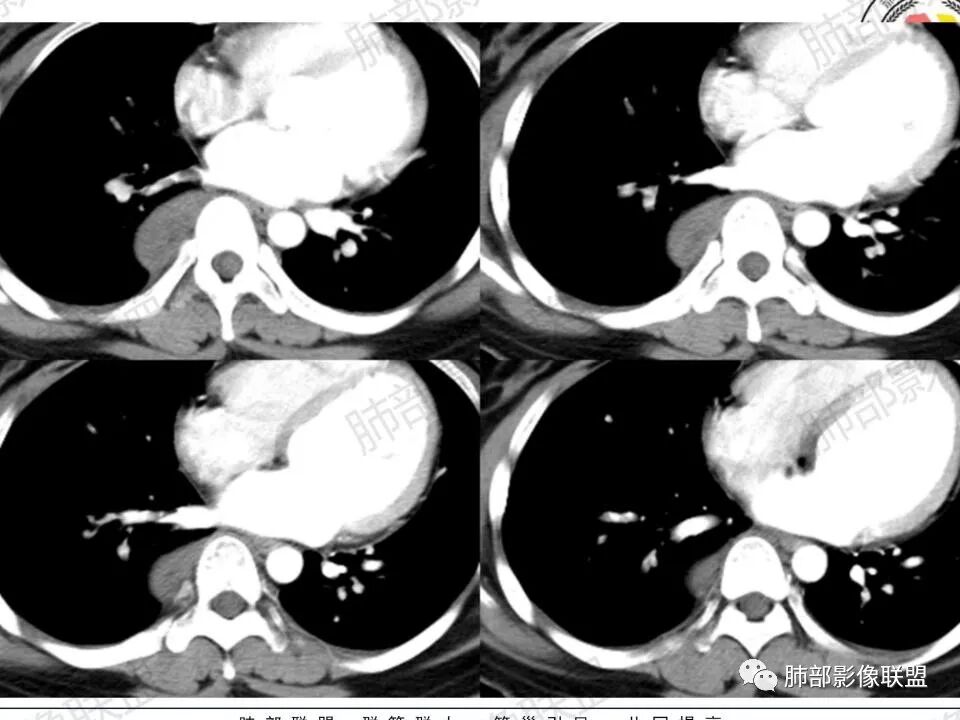

1.青年女性,例行检查发现后纵隔块影,缺乏相关临床症状。

2.右后纵隔脊柱旁上下方向贴伏块影,“肾”形外观,边界清晰,密度不均,中央区域见脂肪密度影引向椎体前方,未见液性密度管腔影及钙化。

3.块影血供动脉来自肋间动脉,且由内后方侧入,其与下腔静脉之间未见回流通道。血管未见破坏,相邻组织未见侵入。

4.块影未延伸至椎管内,未见椎间孔扩大或骨质吸收破坏。

5.轻度渐进性强化。